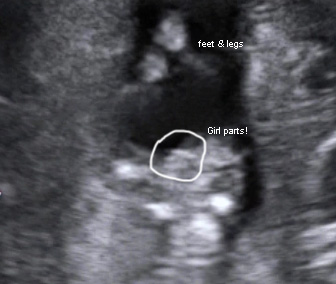

Confirmed girl, nub shots from 11 & 12 weeks, potty shots from 13 & 15 weeks

Confirmed girl by amniocentesis. So excited to be adding another sweet daughter to our family! I hope these pics are helpful - I know I was looking all over for pics to compare to before we found out with certainty.

Potty shot at 15w1d:

Attachment 3215